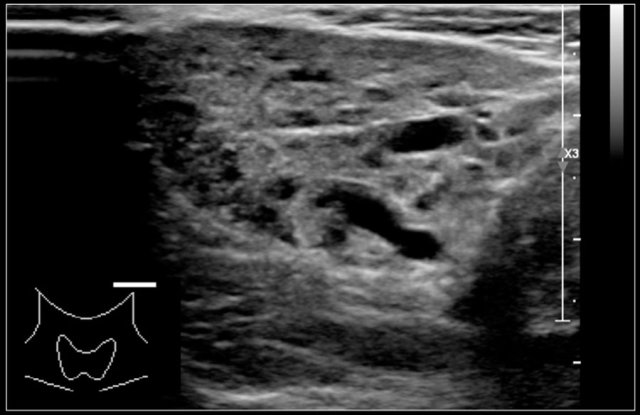

Thyroiditis

The most common forms of thyroiditis are Hashimoto's thyroiditis and Graves disease.

Both Hashimoto's thyreoiditis and Graves disease can present as an enlarged and hyperemic thyroid.

Hashimoto's thyroiditis or chronic lymphocytic thyroiditis is an auto-immune disease.

It presents with hypothyroidism.

Although primarily a disease of the middle-aged it can present in children.

On ultrasound the gland is diffusely enlarged and inhomogeneous.

On color doppler the blood flow is often normal but can be increased like in Graves' disease.